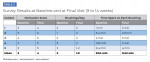

Clinical observations. At the beginning of the case series, all patients exhibited purple and light blue disclosed plaque, indicative of mature, acid-producing biofilm. At the final visit, 9 to 14 weeks later, mature, strong acid-forming plaque was dramatically reduced. In addition, the total surface area covered with plaque was reduced in all patients, with an approximate mean reduction of 34% (range 15% to 45%). Figure 1 and Figure 2 illustrate visibly reduced plaque for patient No. 3 over 9 weeks. Plaque assessment results are summarized in Table 2.

Survey and interview results. Patients were eager to try the Oral-B iO O-R toothbrush and novel Targeted Clean brush head despite the challenges of fixed orthodontia. By the end of the research, patients reported that they greatly enjoyed the O-R toothbrush and novel brush head. Survey data showed that most patients experienced an increased motivation to brush their teeth, with the mean motivation score increasing from 3 to 4. Parents and caregivers reported that their child was re-engaged in managing their own oral health and consequently required less coaxing to brush. Self-reported mean brushing time was relatively flat during the evaluation period (2:34 to 2:42 minutes), increasing by 8 seconds, but the substantial decrease in plaque levels demonstrates the highly efficient plaque removal provided by the brush and novel brush head. Results of the patient survey are summarized in Table 3.